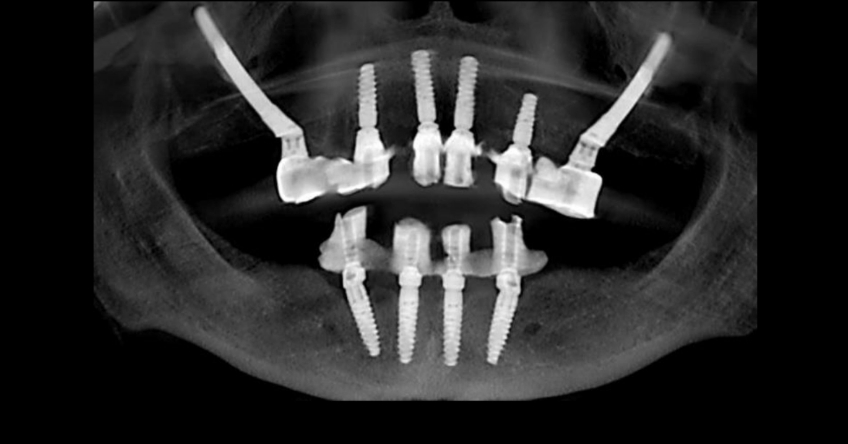

The challenge is that bone availability is limited to her premaxilla, so we must either graft the sinuses to incorporate distal implants or bypass the sinuses and place one ZI bilaterally. Both approaches are perfectly doable and predictable because they’re supported in the scientific peer-reviewed dental literature. They also present nuanced implications that need to be reviewed and understood by the treating team and the patient, who is the ultimate decision-maker.

Her pneumatized sinuses do not allow grafting and implant placement simultaneously. This means we would need a staged approach — perform an initial procedure limited to grafting and a subsequent procedure for implant placement.

This translates to a significant increase in treatment time and financial commitment by the patient. However, bypassing the sinuses and placing a ZI bilaterally would expedite the overall treatment time and represent a financial benefit.

Once the patient understood the nuances between graft vs. a graft-less solution, she opted for a combination of anterior and ZIs instead of grafting the sinuses.